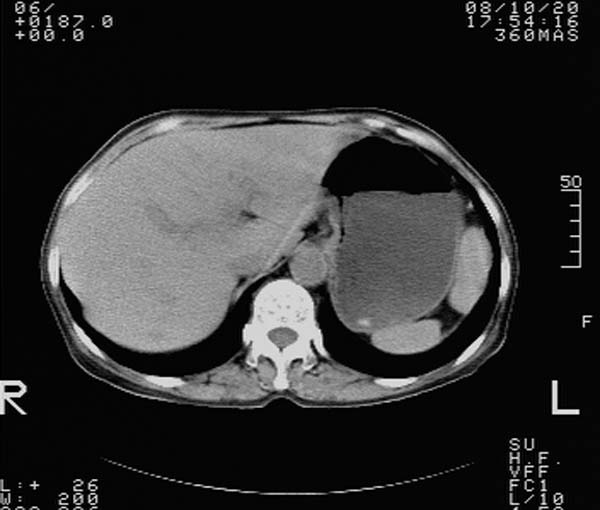

f,67y。反复右上腹痛。余无异常。

前五幅未服造影剂。后面图像有上传重复的。请战友们发表意见。

胆囊结石、胆囊癌伴邻近脏器受侵,不除外黄色肉芽肿性胆囊炎,建议增强扫描。肝多发囊性占位性病变,囊肿或囊性转移。

胆囊内结石,胆囊壁不规则增厚,胆囊胃窦区解剖结构欠清晰,楼主提示为少见病,考虑bouveret综合征?黄色肉芽肿性胆囊炎?肝内多发低密度占位,建议增强或b超

1、胆囊结石、胆囊癌伴邻近脏器受侵,不除外黄色肉芽肿性胆囊炎,建议增强扫描。

2、考虑肝多发囊肿。